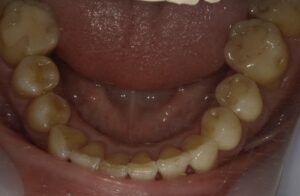

【症例2】50代・矯正は難しいと言われ半ば諦めていたガタガタの改善

「数カ所の歯科医院で相談をしたが、矯正が難しいと言われ諦めかけていた」という50代女性のケースです。前歯が元々欠損しているため真ん中を合わせることはできませんが、ガタガタはIPRや側方拡大を行い治すことができました。

仕上げに前歯のすり減りをダイレクトボンディングで直し、より整った印象にしています。

- 治療方法: ワイヤー矯正上下

- 治療期間: 12ヶ月

- 治療費用: 77万円(税込)

- 治療のリスク・デメリット:ブラックトライアングル

- ポイント: 比較的短期間のプランで、前歯の見た目と清掃性を大幅に向上させました。